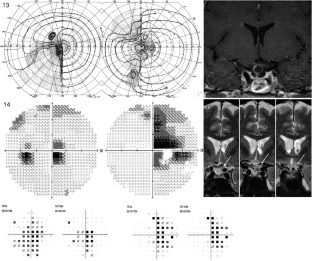

The hemi-decussation at the optic chiasm creates the potential for crossed and uncrossed fibers to be affected in isolation or in various combinations of nerve, chiasm and tract, with patterns that reflect the retinotopic arrangement of axons. We present seventeen cases that illustrate the field defects that can result and review the literature to create a taxonomy of junctional visual field defects. The complete junction defect is blindness in one eye and loss of the entire temporal field of the other. The classic junctional scotoma combines optic neuropathy in one eye with upper temporal hemifield loss in the other, and is often a sign of ventral compression. The less frequent atypical junctional scotoma involves the lower temporal hemifield and has a higher frequency of dorsal compression or non-compressive pathology. There are the monocular defects in the temporal (‘junctional scotoma of Traquair’) or nasal hemifield, the latter of which is rarely if ever due to a pituitary adenoma. Highly asymmetric bitemporal defects with or without a central scotoma and the paradoxical junctional scotoma occur by extension of the lesion causing the junctional scotoma of Traquair. The posterior junction defect results from combined damage to the optic chiasm and optic tract. Recognizing these various patterns is important clinically as junctional defects have the same localizing significance as bitemporal defects and are being encountered more often. In addition the probability of certain types of pathology varies with the type of junctional defect.

Figures in cases 1, 6 and 12 are adapted with permission from: Barton JJS, Benatar M. Field of Vision: a manual and atlas of perimetry, Humana Press (now Springer Nature), Totowa NJ, 2003, and those of cases 7, 9 and 15 are reproduced with permission from www.neuro-ophthalmology.ca. We thank Briar Sexton for sharing case 9 with us.

Barton, J.J.S., Özturan, G. The varieties of junctional scotoma: 17 cases, a review, and a taxonomy. Eye 39, 1673–1687 (2025). https://doi.org/10.1038/s41433-025-03789-z